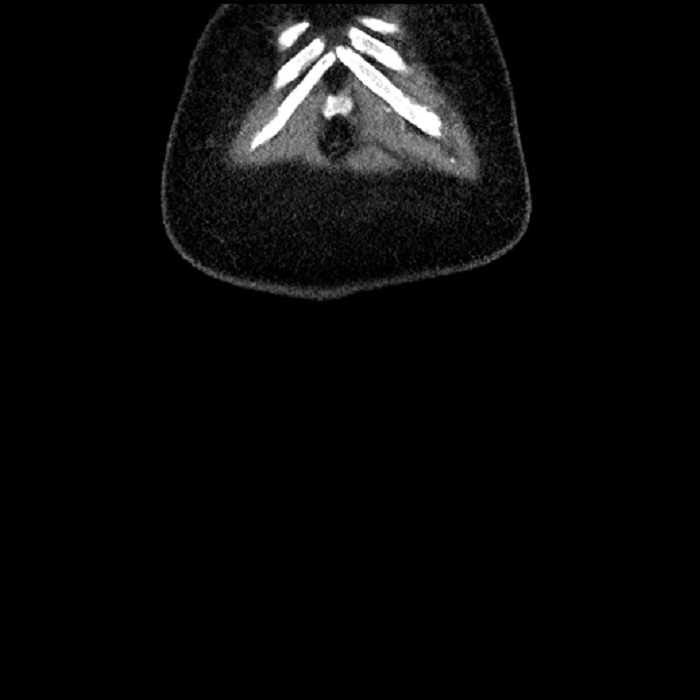

• High grade stenosis of the left common iliac artery, with the left internal and external iliac arteries remaining patent

High grade stenosis of the left common iliac artery. The left external and internal iliac arteries are patent.